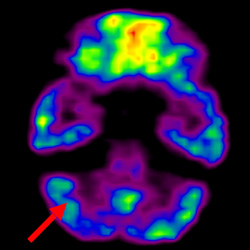

細(xì)胞治療前PET CT掃描顯示神經(jīng)組織中的藍(lán)/黑色區(qū)域,表明腦癱引起的大腦損傷。

腦癱細(xì)胞療法, 腦癱治療

細(xì)胞治療后,藍(lán)色和黑色區(qū)域減少,并且看到更活躍的區(qū)域。這表明損傷減少并改善了大腦功能。